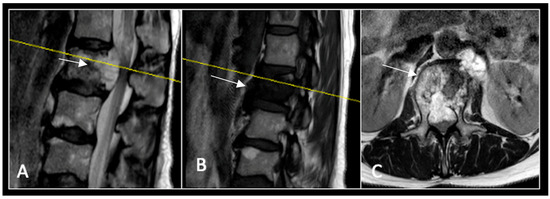

A 73-year-old male presented with an eight-month history of neck pain that was exacerbated on lying flat. He denied any symptoms of myelopathy and radiculopathy. He did not have any constitutional symptoms of malignancy. Past medical history included hypertension, renal cysts, and an ascending thoracic aneurysm. Examination was unremarkable. Diagnostic whole-spine MRI imaging demonstrated a large lobular mass localised to the cervical spine (Figure 2). Biopsy confirmed a conventional chordoma, and he underwent separation surgery followed by adjuvant proton beam therapy. Postoperative surveillance imaging at 12 months demonstrated stable disease (Figure 3).

Figure 2.

MRI demonstrating a destructive lobular lesion localised to the C2 vertebra (chordoma) (arrow). There is significant left-sided extension into the paravertebral tissues laterally and epidural space centrally with indentation of the cord. The yellow line on the sagittal images denotes the level at which the corresponding axial section was obtained. (A) T2-W sagittal; (B) T1W sagittal; (C) T2W axial.